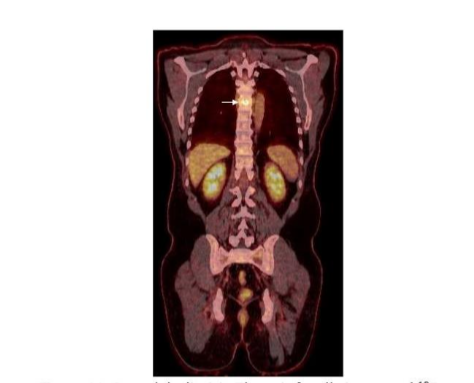

Figure 11.

Spondylodiscitis. There is focally increased ¹⁸F-FDG uptake in the mid thoracic spine (arrow) on the coronal PET/CT image.